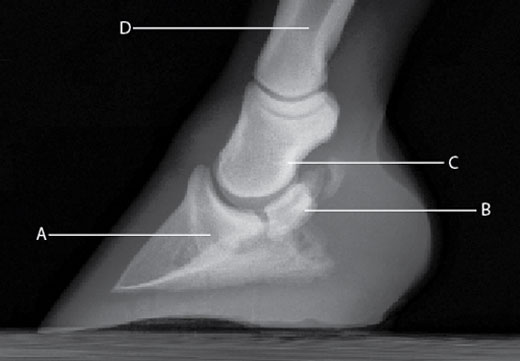

El síndrome navicular en los caballos es un arduo desafío en el tratamiento veterinario. Una forma de aliviar el dolor y reducir la inflamación asociada con esta condición consiste en inyectar un corticosteroide y ácido hialurónico —una combinación que tiene excelentes tasas de éxito a corto y a largo plazo— directamente en la bursa navicular. Puesto que la inyección en la bursa navicular es más difícil que la inyección en la articulación interfalángica distal (DIPJ, por sus siglas en inglés), el tratamiento sería más simple si los medicamentos pasaran siempre a través de la barrera biológica entre estos dos espacios sinoviales. Los dos espacios raramente se comunican de manera directa, pero las pequeñas sustancias de peso molecular se dispersarán en la bursa navicular desde la DIPJ. Sin embargo, las moléculas más grandes como el ácido hialurónico no pueden dispersarse. Un estudio en 11 caballos adultos clínicamente normales evaluó si la acetonida triamcinolona, un corticoesteroide comúnmente utilizado en el tratamiento del síndrome navicular, se dispersaría de la DIPJ a la bursa navicular, si la difusión sería directa o sistémica, y si la adición de ácido hialurónico afectaría esta difusión.

El estudio se realizó en dos fases. En la primera fase, se inyectó triamcinolona más solución de Ringer Lactato en la DIPJ de ambas extremidades anteriores de siete caballos. Se obtuvo el líquido sinovial de la bursa navicular a los 30 minutos y a una, tres, seis y nueve horas después de la inyección. Además, se evaluó este líquido para determinar en qué momento ocurrió la concentración más alta de triamcinolona. La concentración más alta de triamcinolona en la bursa navicular ocurrió seis horas después de la inyección en la DIPJ. En la segunda fase, se les inyecto a 11 caballos triamcinolona más solución de Ringer Lactato en una DIPJ de la extremidad anterior y una inyección de triamcinolona más ácido hialurónico en la otra extremidad anterior. Seis horas después de la inyección, se evaluó las muestras del líquido sinovial obtenidas de las bursas naviculares de las extremidades anteriores y posteriores de cada caballo. Las muestras de las extremidades posteriores sirvieron como un grupo de control sistémico ya que la absorción sistémica de la triamcinolona ocurre después de una inyección articular.

No se detectó triamcinolona en las muestras de la DIPJ previas a la inyección en los caballos de la segunda fase del estudio. Se encontró triamcinolona en todas las muestras de la bursa navicular de las extremidades posteriores después de la inyección y no se vio una diferencia significativa en las concentraciones de triamcinolona entre las extremidades anteriores que recibieron ácido hialurónico y aquellas que no. Se detectó una concentración significativamente mayor de triamcinolona en la bursa navicular de las extremidades anteriores que en la bursa navicular de las extremidades posteriores, lo cual representa un grado menor de absorción sistémica. La bursografía navicular realizada después de las inyecciones reveló que no existe ninguna comunicación directa entre la DIPJ y la bursa navicular. Aunque las concentraciones individuales de triamcinolona en el líquido sinovial variaron ampliamente, los resultados demuestran que la triamcinolona se difunde rápidamente entre la DIPJ y la bursa navicular de los caballos clínicamente normales y que la adición de una sustancia de alto peso molecular no afecta este movimiento. Estos resultados allanan el camino para nuevas investigaciones sobre los efectos, tanto positivos como negativos, del síndrome navicular en la permeabilidad de la membrana sinovial, la estructura de ácido hialurónico y el metabolismo de los fármacos en una articulación inflamada. Los profesionales de la veterinaria en equinos han sospechado desde hace tiempo que existe una relación, y ahora hay más datos que apoyan el tratamiento del síndrome navicular mediante inyecciones en la DIPJ.